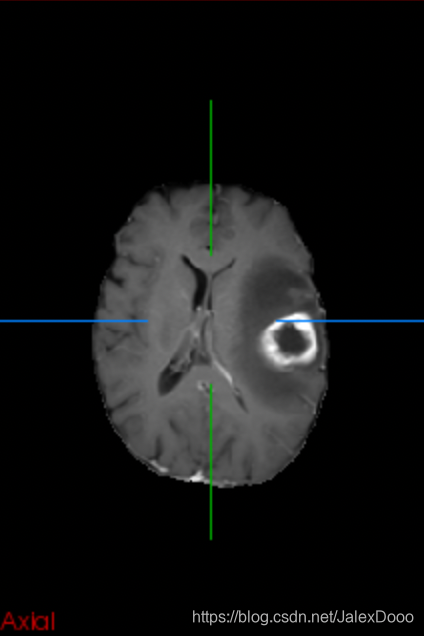

用在了大脑胶质瘤分割上,2D的处理方式,论文也是2D的处理形式,实在差劲;然后改成3D处理,还是差劲。

2D处理